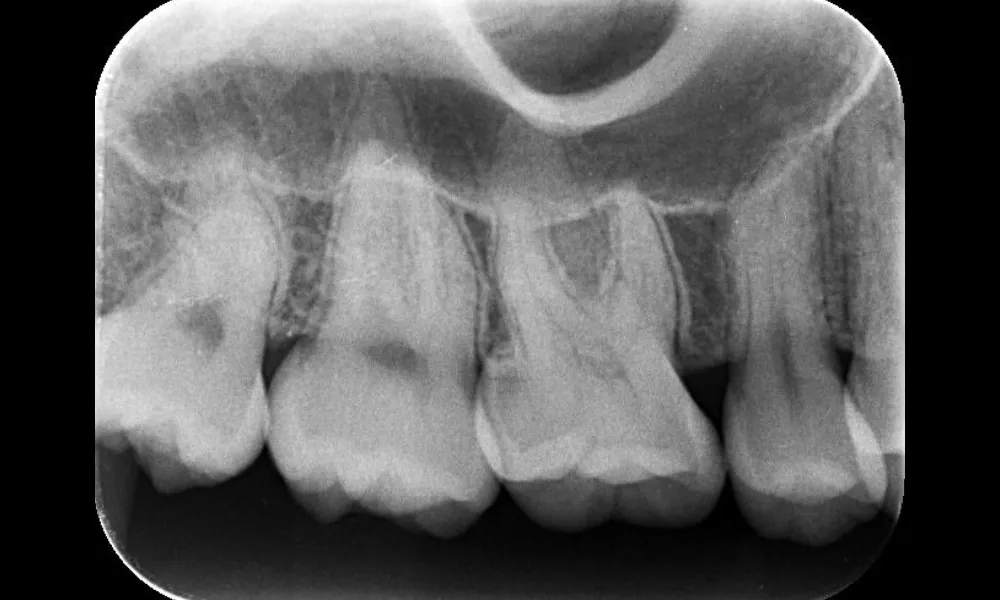

| 主訴 | 親知らずが虫歯になっている |

| 治療期間 | 60分 |

| 治療費 | 1歯 2,000~5,000円 |

| 治療内容 | 上下の親知らずを同日に抜歯を行い縫合し、翌日以降に消毒、抜糸を行った。 |

| 治療のリスク | 術後の疼痛、腫脹、痺れ |